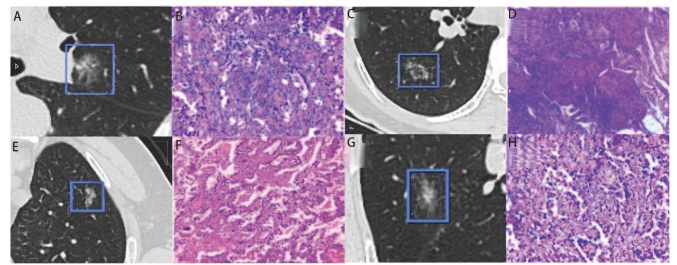

Methods: This retrospective study analyzed 229 PSN from 222 patients who underwent pulmonary nodule resection at Lanzhou University Second Hospital between October 2020 and February 2025. According to pathological results, 45 cases of benign lesions and precursor glandular lesion were categorized into the non-malignant group, and 184 cases of pulmonary malignancies were categorized into the malignant group. All patients underwent preoperative chest computed tomography (CT), and AI software was used to extract imaging feature parameters. Univariate analysis was used to screen significant variables; variance inflation factor (VIF) was calculated to exclude highly collinear variables, and LASSO regression was further applied to identify key features. Multivariate Logistic regression was used to determine independent risk factors. Based on the selected variables, five models were constructed: Logistic regression, random forest, XGBoost, LightGBM, and support vector machine (SVM). Receiver operating characteristic (ROC) curves were used to assess the performance of the models.

Results: The independent risk factors for the malignancy of PSN include roughness (ngtdm), dependence variance (gldm), and short run low gray-level emphasis (glrlm). Logistic regression achieved area under the curves ( AUCs) of 0.86 and 0.89 in the training and testing sets, respectively, showing good performance. XGBoost had AUCs of 0.78 and 0.77, respectively, demonstrating relatively balanced performance, but with lower accuracy. SVM showed an AUC of 0.93 in the training set, which decreased to 0.80 in the testing set, indicating overfitting. LightGBM performed excellently in the training set with an AUC of 0.94, but its performance declined in the testing set, with an AUC of 0.88. In contrast, random forest demonstrated stable performance in both the training and testing sets, with AUCs of 0.89 and 0.91, respectively, exhibiting high stability and excellent generalizability.